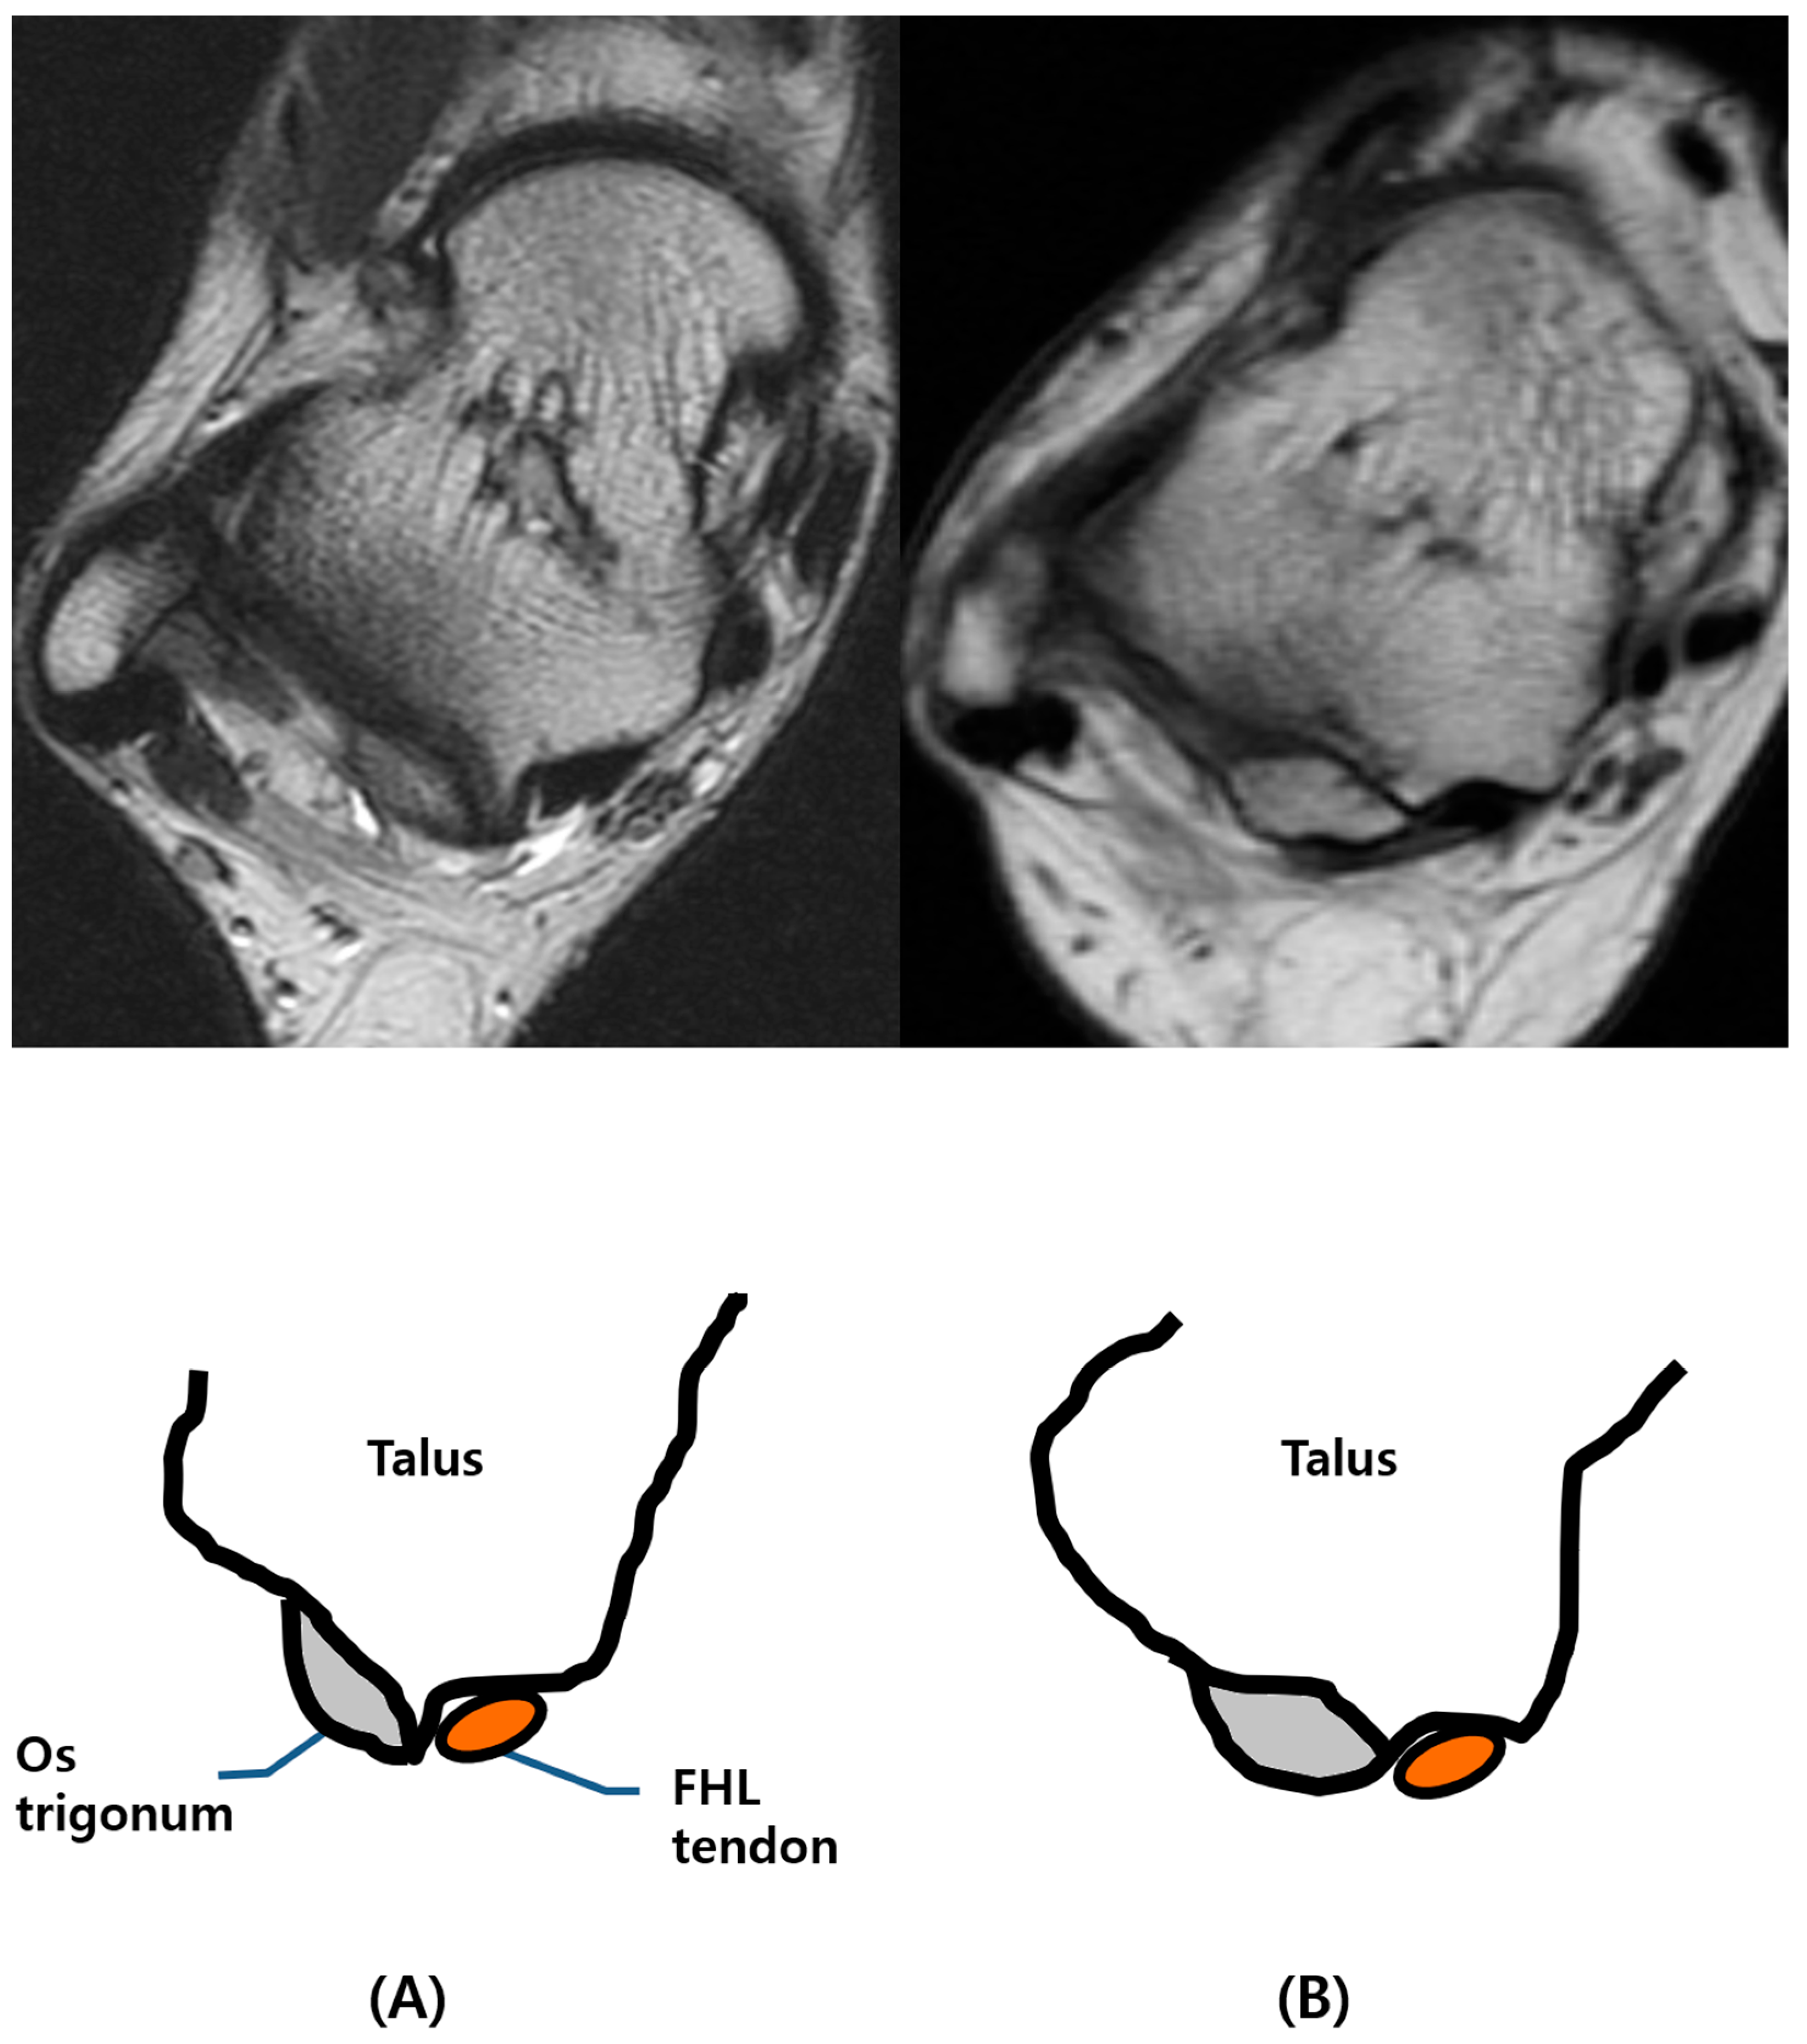

First, the images acquired using each MR sequence were reviewed by reader 1, and dimensions of the os trigonum were recorded, including anterior–posterior (AP) and transverse diameter on an axial T2-weighted or PD FS image, and the size of the accessory facet on a sagittal T2-weighted FS or PD FS image. Furthermore, the count of the number of ossicles was recorded by the same reader. Second, two reviewers classified all cases of os trigonum into two different types: type I and type II. Type I os trigonum is represented as the medial border of the ossicle not overlying the posterior process of the talus and an intact groove for the tendon of flexor hallucis longus (FHL) in cases of os trigonum. In cases of os trigonum where the medial border of the ossicle invading groove for the FHL tendon was seen, we considered the cases type II (Figure 1).

Figure 1. Different types of os trigonum. (A) Type I os trigonum with intact FHL groove, (B) type II os trigonum as the medial border of the ossicle-invading groove for FHL tendon.